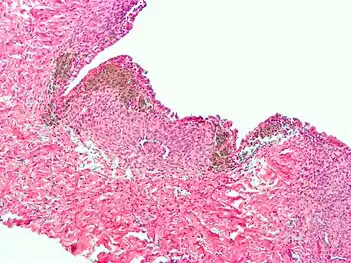

Endometriosis, abdominal wall

Micrograph showing endometriosis (right) and ovarian stroma (left)

Micrograph of the wall of an endometrioma. All features of endometriosis are present (endometrial glands, endometrial stroma and hemosiderin-laden macrophages).

Histopathology

For a histopathological diagnosis, at least two of the following three criteria should be present:[110]

- Endometrial type stroma

- Endometrial epithelium with glands

- Evidence of chronic hemorrhage, mainly hemosiderin deposits